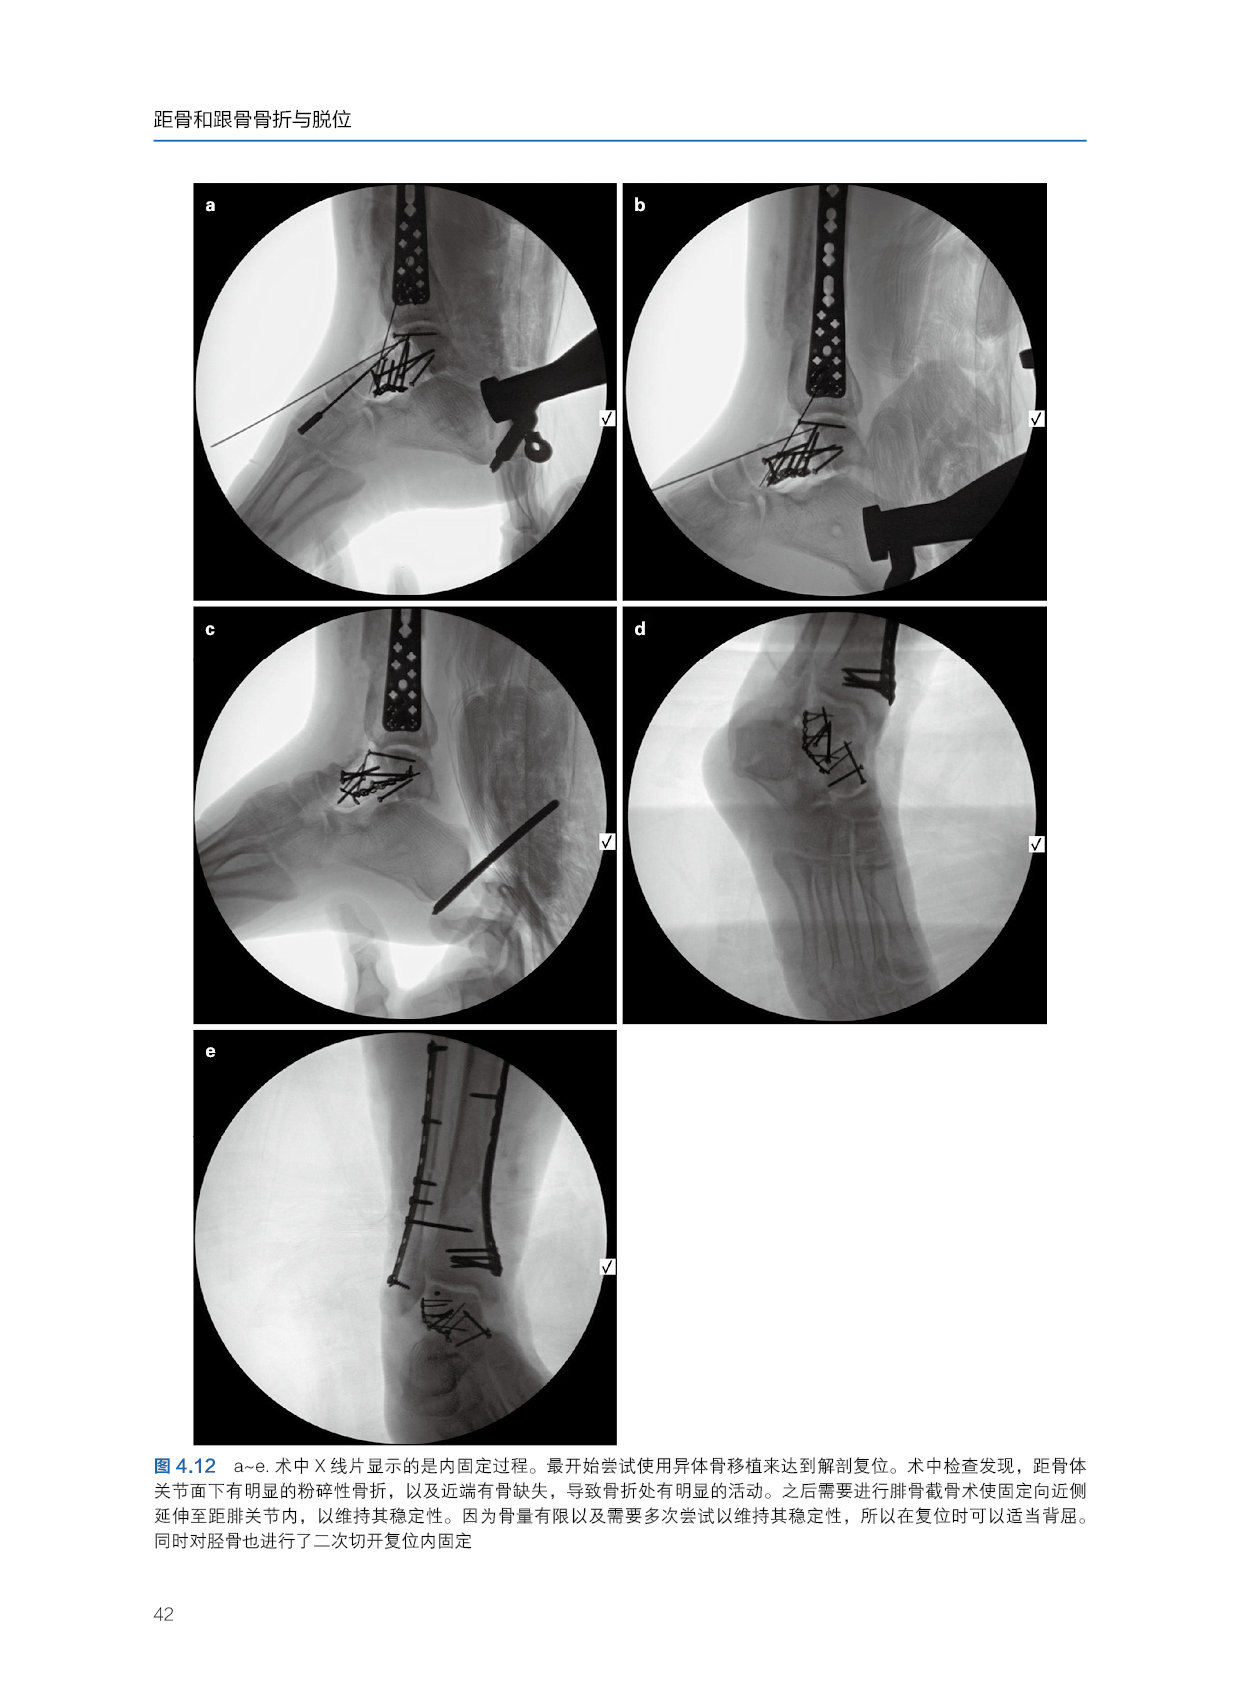

该书围绕本学科的常规手段,采取基础原则和病例精讲的形式,对距骨和跟骨骨折与脱位的每个关键点进行深入浅出的解读,详细讲解足部损伤疗效分析、足部损伤的初步评估、距骨骨折基础、距骨颈骨折、距骨后突骨折、距骨顶骨软骨损伤、全距关节脱位。每个关键步骤均配有文字叙述,深入浅出、图文并茂。